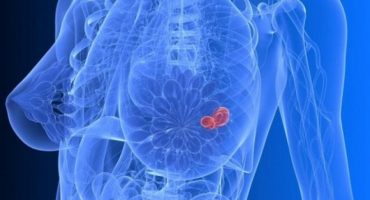

Senologia

Prestazioni: visita specialistica ecografia mammella sfoglia la brochure Èquipe Responsabile: Dott. Giovanni Steffano Dott.ssa Daniela Mattarel